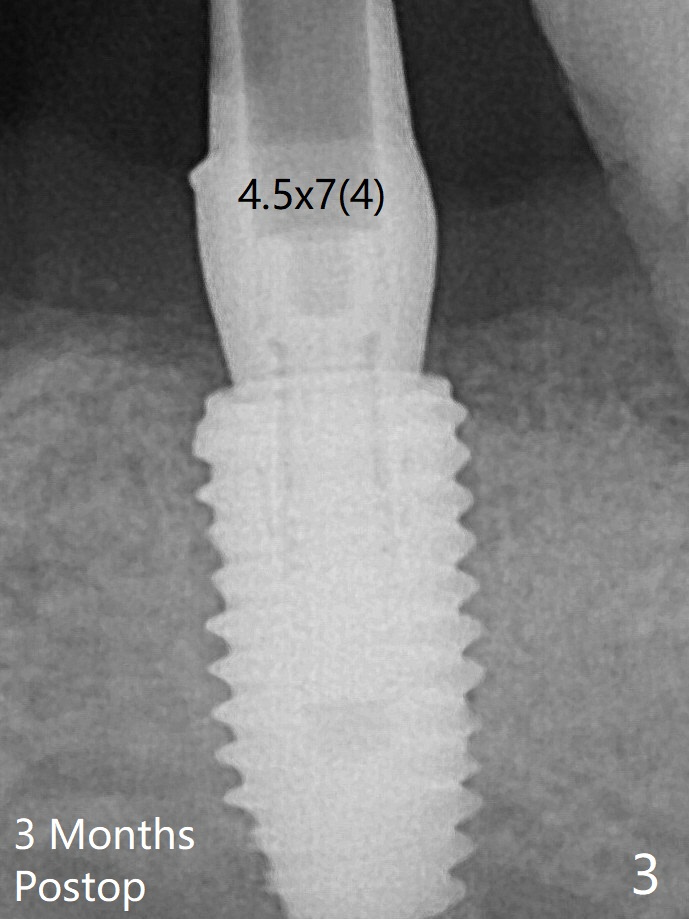

更换4.5x7(4)毫米UF基台就位仿佛改善(图三),降低基台高度后取模。